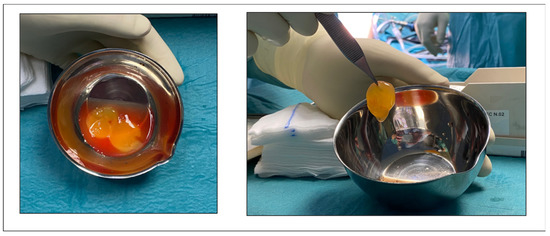

2.4. Surgical Technique